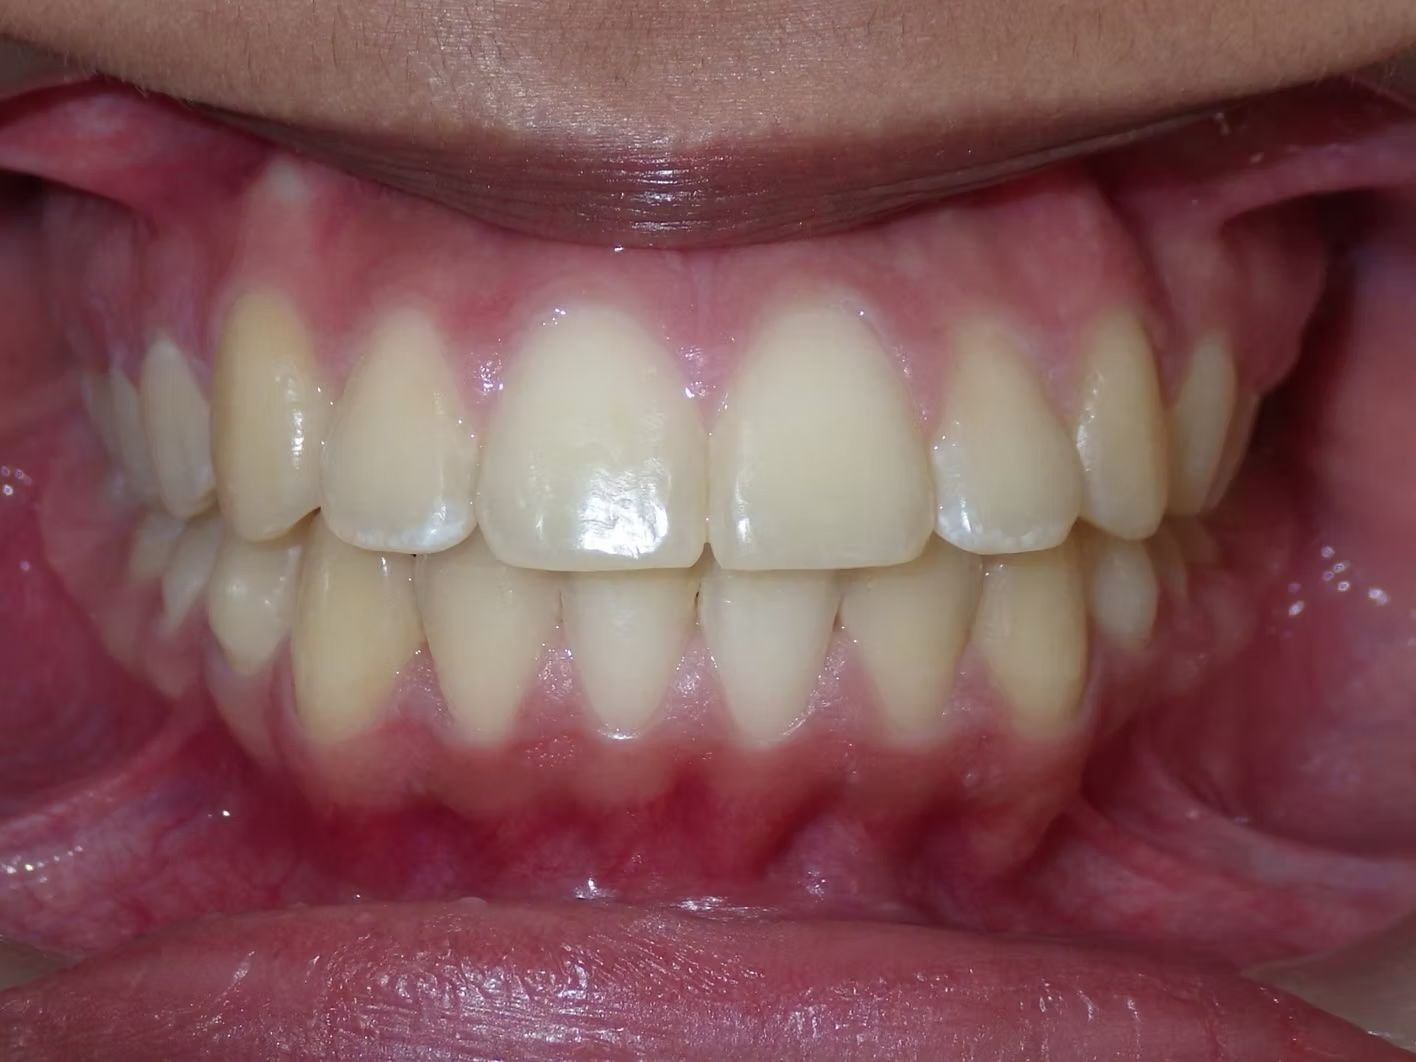

BRIANNA

Brianna's lower left 1st premolar was completely in a brodie bite (outside the normal arch) and her top and bottom teeth were very crowded. Dr. Freedman corrected her bite and crowding without removing any teeth.